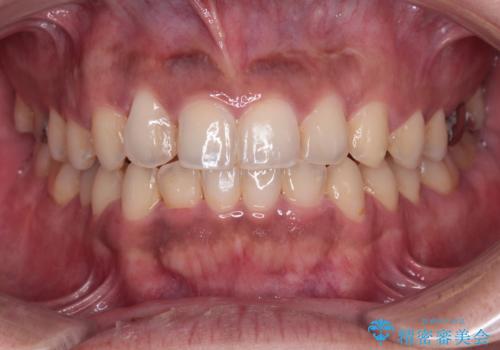

- 学生時代に行った抜歯矯正の後戻りで、隙間ができてしまったことを気にして来院された患者様です。

マウスピース矯正を検討されていましたが、後戻りの隙間が非常に大きく、奥歯を前方に移動させる必要があるため、ワイヤー装置にて矯正治療を行うこととしました。

舌の突出癖が非常に強く、その影響で隙間ができてしまったので、舌のトレーニングをしっかりと行っていただきました。

上顎歯列は歯の移動量が少なかったため、セラミッククラウンは装置を装着せずに治療を終えることができました。